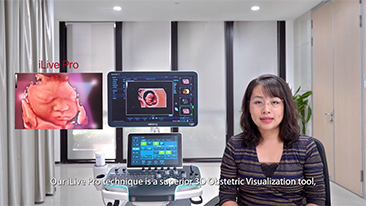

??? ??? ??? ???? ? ?? ???? ??? ? ?????

?? ?? ?? ??? ?? ?? ?? ???? ?? ???? OBG ?????? ?????. ?? ??, ?????(CNS) ??? ?? ?? ??? ?? ? ?????. ???? ?? ??? ?? ??? ??? ??? ?? MSP? 2D ????? ?? ???? ?????. ??? ?? ?? ? ??? ??? ???? ?? ???? ? ????.